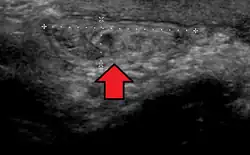

No diagnóstico de hérnias abdominais, a imagem é o principal meio de detectar hérnias diafragmáticas internas e outras hérnias não palpáveis ou não suspeitas. A tomografia computadorizada com múltiplos detectores (TCMD) pode mostrar com precisão o local anatômico do saco de hérnia, o conteúdo do saco e quaisquer complicações. A TCMD também oferece detalhes claros da parede abdominal, permitindo que as hérnias sejam identificadas com precisão.[9]